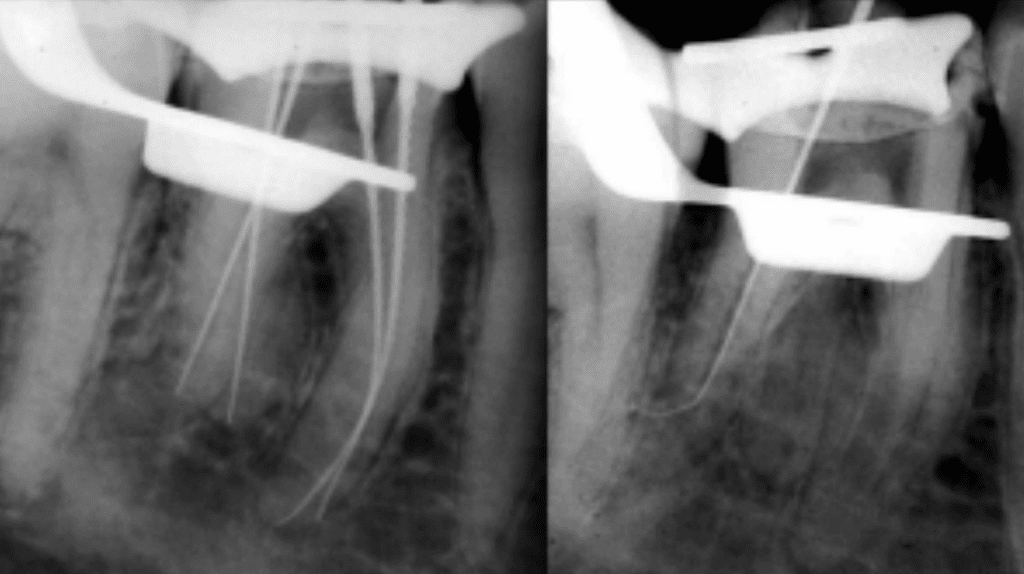

Step 1: Confirm Working Length

- Use a size 10 file with your apex locator.

- Get a stable, repeatable reading before anything else goes in.

Step 2: Establish a Smooth Glide Path

Work your way: 10 → 15 → 20. Pre-curve every file. Use light watch-winding and gentle strokes.